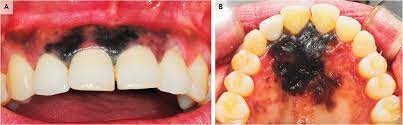

Oral Cancer

In rare cases, benign lesions that don't require treatment may transform into oral malignant melanoma, a type of oral cancer. A doctor will look at a range of factors to see if the lesion qualifies as melanoma. According to a research article published in the Journal of Indian Academy of Oral Medicine and Radiology, melanoma constitutes only 3–5% of all cutaneous malignancies, and oral melanoma is an aggressive neoplasm which accounts for less than 0.5%.

If you believe you have oral cancer symptoms, we recommend leaving the diagnosis up to the professionals and speaking to your doctor. If you exhibit symptoms, they may perform a biopsy (laboratory tests of your tissue) to confirm melanoma.

Remember that cancer is a rare cause of any dark spots in your mouth. A more benign explanation is much more likely, so don't stress. You've done a great job informing yourself of the possible causes, so be sure to make the next step for success and schedule an appointment or regular check-ups with your doctor.